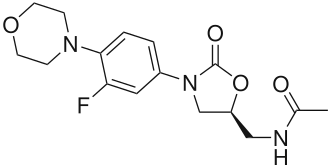

| ИЮПАК | (S)-N-({3-[3-фторо-4-(морфонил-4-ил)фенил]-2-оксо-1,3-оксазолидин-5-ил}метил)ацетамид |

| Брутто-формула | C16H20FN3O4 |

| Молярная масса | 337.346 г/моль |